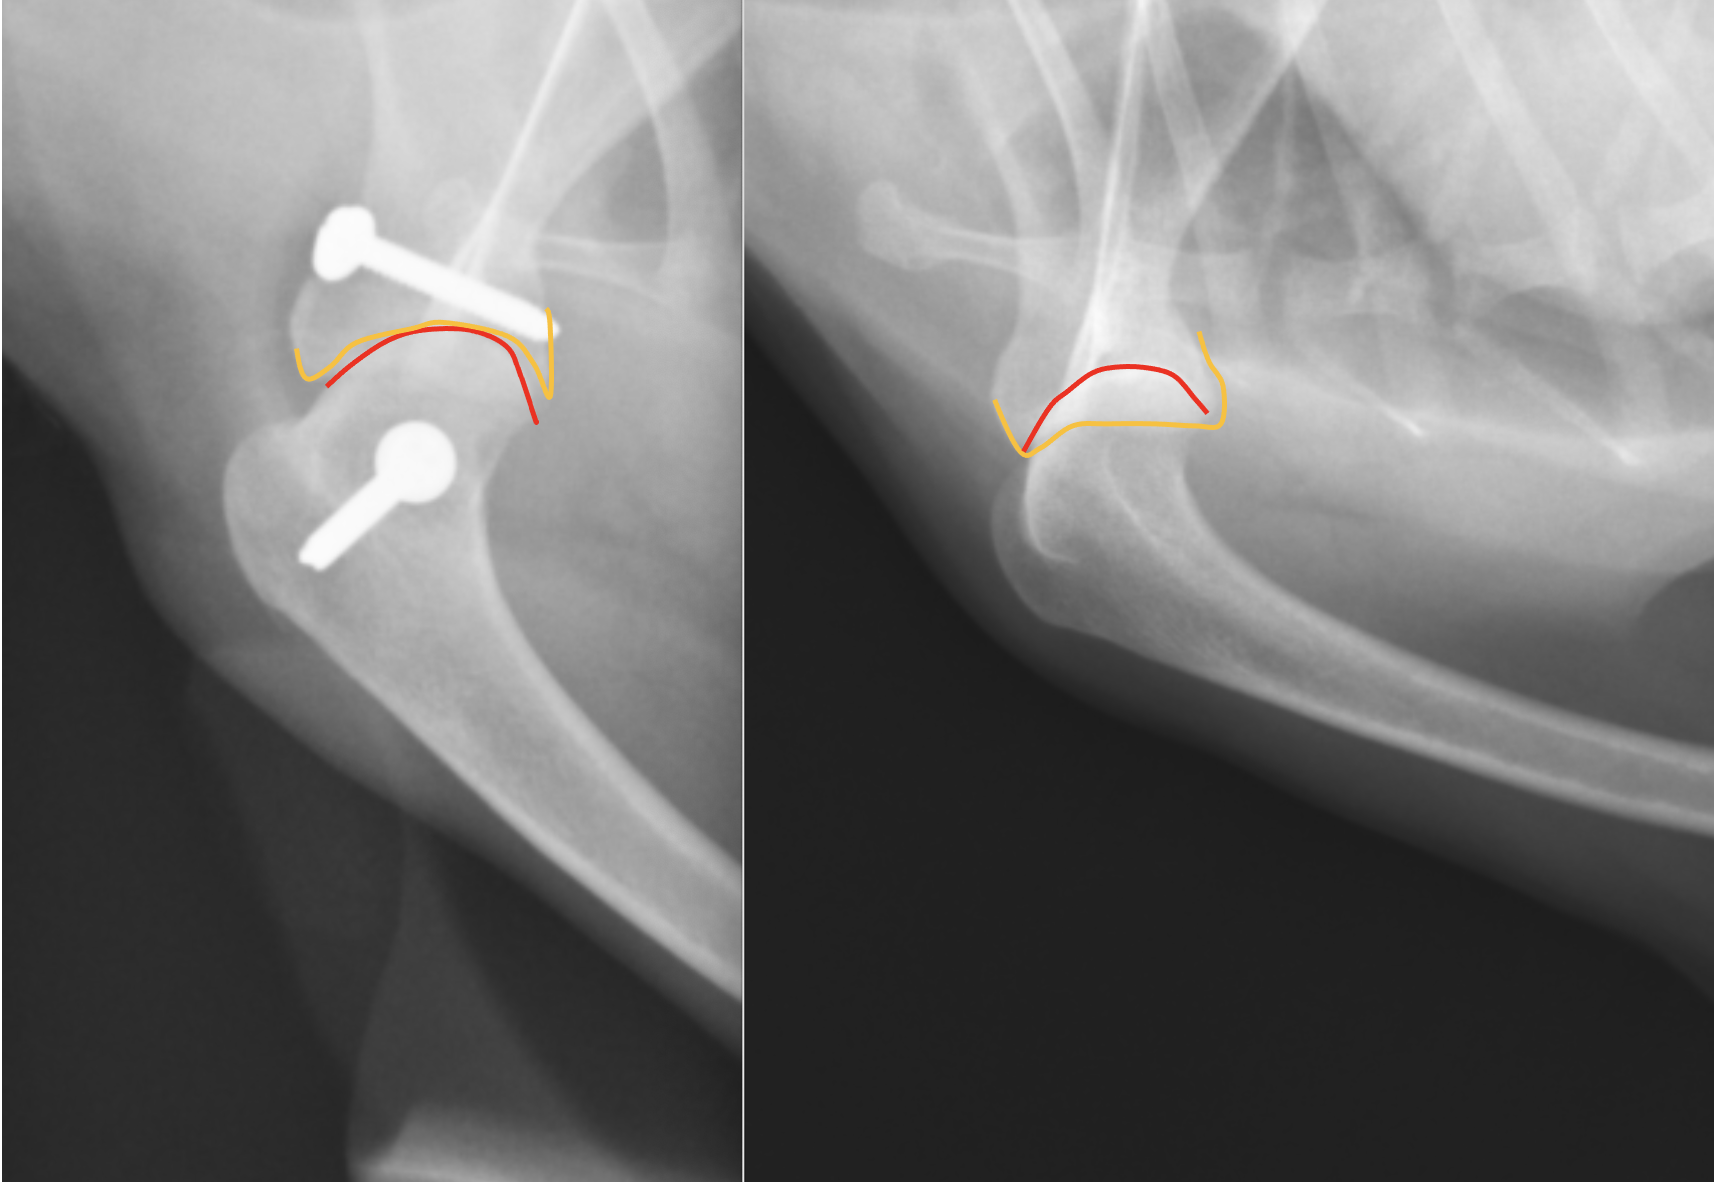

横から見たレントゲンです。右が術前、左が術後です。こちらも線を引くと

右のレントゲンではオレンジと赤のラインが全く合っていなかったのが、左の術後ではピッタリとあっているのがわかると思います。